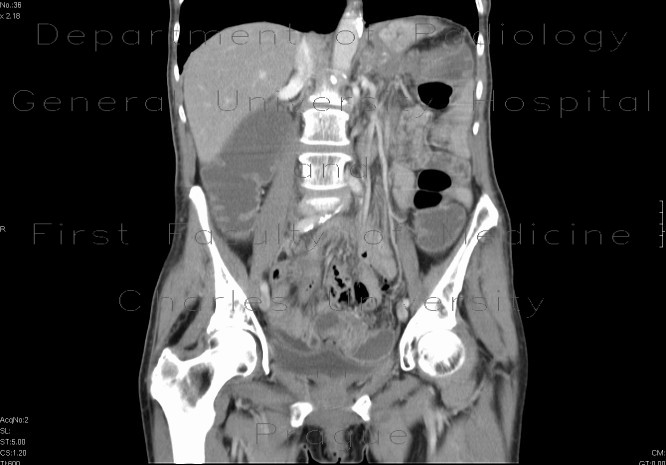

Case Report: Solitary Ischaemic Small bowel stenosis

Case report: Solitary ischaemic small bowel stenosis stenosis in the patient presented here and was confirmed by histological examination. In conclusion, the present case illustrates the need to ... Retrieve Document